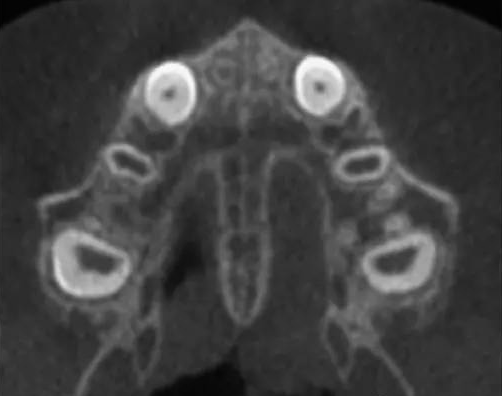

其实成年后,能否做扩弓矫正关键的还是要看,腭中缝的发育状况,腭中缝发育受遗传、环境、创伤、等多种因素影响,有着很大的个体差异,尽管大部分人18岁腭中缝就已经完全闭合了,但并不是所有人18岁以后就完全闭合了,一定要拍高清口腔全景片确认腭中缝发育情况,从而判断是否能做扩弓矫正。而不是单独通过年龄来判断。